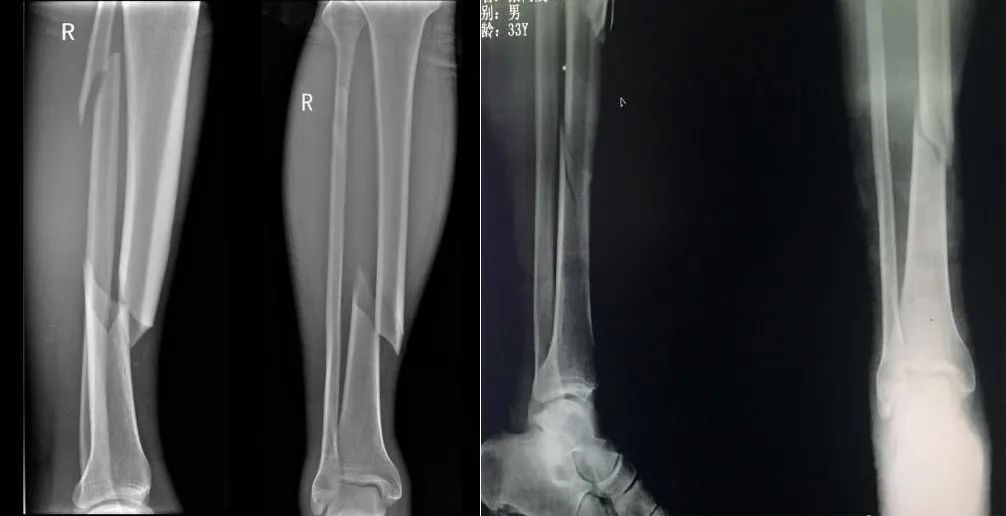

AO / OTA骨(gu)(gu)折脫位的(de)阿拉伯(bo)數字分(fen)型(xing)將脛骨(gu)(gu)干骨(gu)(gu)折設定為(wei)4(脛骨(gu)(gu))2(骨(gu)(gu)干)。A型(xing)對(dui)應(ying)有(you)一條骨(gu)(gu)折線(xian)的(de)簡(jian)單骨(gu)(gu)折。這是(shi)最(zui)常見的(de)類型(xing)。B型(xing)骨(gu)(gu)折有(you)個(ge)中間楔形骨(gu)(gu)折塊。C型(xing)骨(gu)(gu)折是(shi)由高能量損傷引起的(de),為(wei)粉碎性節段性骨(gu)(gu)折。

- 脛骨(gu)(gu)(gu)干簡單骨(gu)(gu)(gu)折或(huo)粉碎(sui)性骨(gu)(gu)(gu)折(AO 42A-C)

- 脛骨干(gan)多段性骨折(zhe)(AO 42C)